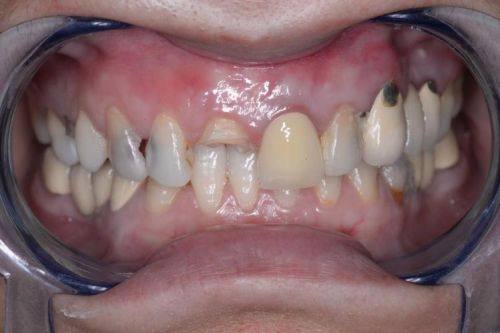

牙体缺损修复:以成熟修复技术为核心,修复体边缘密合度高,能有效修复牙齿形态与功能,美学成效自然逼真。

美学修复(全瓷冠、嵌体、贴面):配备智能化比色系统,精细匹配天然牙色泽,修复后牙齿形态自然,满足患者的口腔美学需求。